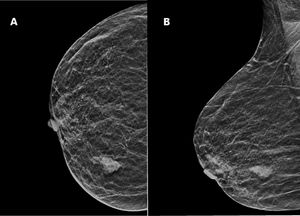

Mujer de 71 años que consultó por un nódulo en el seno derecho. En la exploración física se palpó un nódulo de aproximadamente 2cm en el cuadrante externo de la mama derecha, sin ganglios linfáticos axilares, supraclaviculares o cervicales.

Se realizó una mamografía y ecografía, mostrando una masa irregular de 18mm sin conexión con la piel o el pezón (BIRADS5) (fig. 1A y B).

El CSM es más frecuente en mujeres. Tan solo existen 2 casos masculinos descritos en la literatura13,19, de los cuales solo uno cumple con claridad los criterios para el diagnóstico19. La forma de presentación clínica en la mayoría de los casos es como tumoración palpable en la glándula mamaria. Las pruebas complementarias (mamografía, ecografía y resonancia nuclear magnética) muestran lesiones nodulares, espiculadas, sugestivas de malignidad y nos son de utilidad para descartar afectación de la piel y/o pezón.